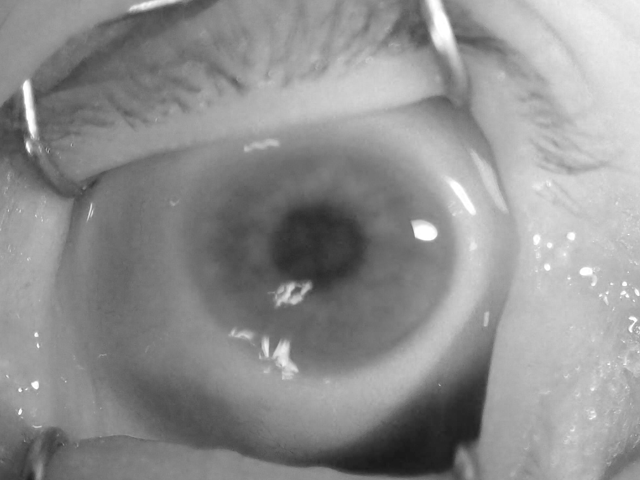

IV-B Visual Inspection of Post-Mortem Changes

We have taken the effort to carefully examine the samples throughout the time period since death for all subjects, and confront the observed changes with medical knowledge. This yielded a qualitative evaluation of post-mortem changes to the iris reported in this Section. Having both NIR and VIS images is crucial for such assessment, as these two types of illumination often reveal different appearance of the iris when changes to the cornea and the anterior chamber are present. This is shown in Fig. 3, where visible-light samples are compared against near-infrared samples for the same eye. Such differences are also reported on in the works of Aslam et al. [20] and Trokielewicz et al. [21] related to the disease influence on iris recognition performance. Both studies show that the NIR illumination typically used in iris recognition cameras is capable of alleviating corneal opacification effects to some extent.

A summary of example post-mortem changes that appear in the eye is presented in Fig. 2, together with a timeframe for a selected subject. It must be noted, however, that the dynamics of these changes are heavily subject-dependent and can happen with different rapidity, intensity and prevalence on the appearance of iris tissue.

First, a corneal opacification progresses with time since death, and it becomes visible after a few days post-mortem (e.g., 95 hours, or 4 days, after death, as depicted in Fig. 2). Second, a wrinkling of the corneal surface is expected to appear (e.g., 359 hours, or 15 days, as shown in Fig. 2). At this point, a strong influence on the automatic image segmentation procedures can be anticipated, as the iris tissue becomes less visible and additional patterns and light reflections emerge. Third, a loss of intraocular pressure in the eyeball due to post-mortem biochemical changes can be observed (e.g., 574 hours, or 24 days, as illustrated Fig. 2), causing the eye to slowly collapse into the eye socket. At this point in time, iris recognition methods are expected to seldom work, as the iris pattern is severely obstructed and thus challenging for iris image segmentation. Finally, after about a month, the eyeball was observed to dry out completely, leaving no traces of a healthy iris structure.

Contrary to initial predictions, we did not come across any sample that would be affected by tache noire. Also, the severe corneal opacification was visible in original VIS samples only, while NIR and R images worked in favor of exposing post-mortem iris texture better than original VIS samples, as depicted in Fig. 3.